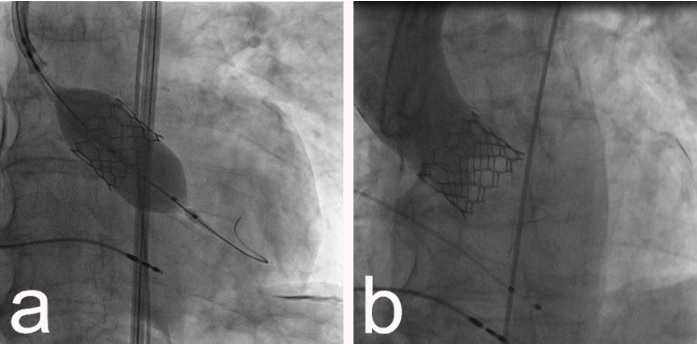

A TAVI é uma forma menos invasiva de substituir a válvula para pessoas consideradas de alto risco para cirurgia convencional. Ao invés de cortar o esterno, como na cirurgia de coração aberto, a válvula é guiada através de uma abordagem transcateter. Isso significa que a válvula é entregue em um cateter enquanto comprimida e, em seguida, levada através de uma pequena incisão ou corte no vaso sanguíneo, geralmente na artéria femoral, sendo guiada até o coração. Outras abordagens, como o acesso via um vaso sanguíneo diferente em outro lugar pode ser mais adequado para aguns casos, mas é raro.

Com orientação de fluoroscopia e ecocardiograma (ECO), a nova válvula é colocada sobre a válvula nativa. O objetivo do procedimento é substituir a válvula sem anestesia profunda prolongada e de forma minimamente invasiva, reduzindo o risco do procedimento, as chances de complicações e o tempo de internação.